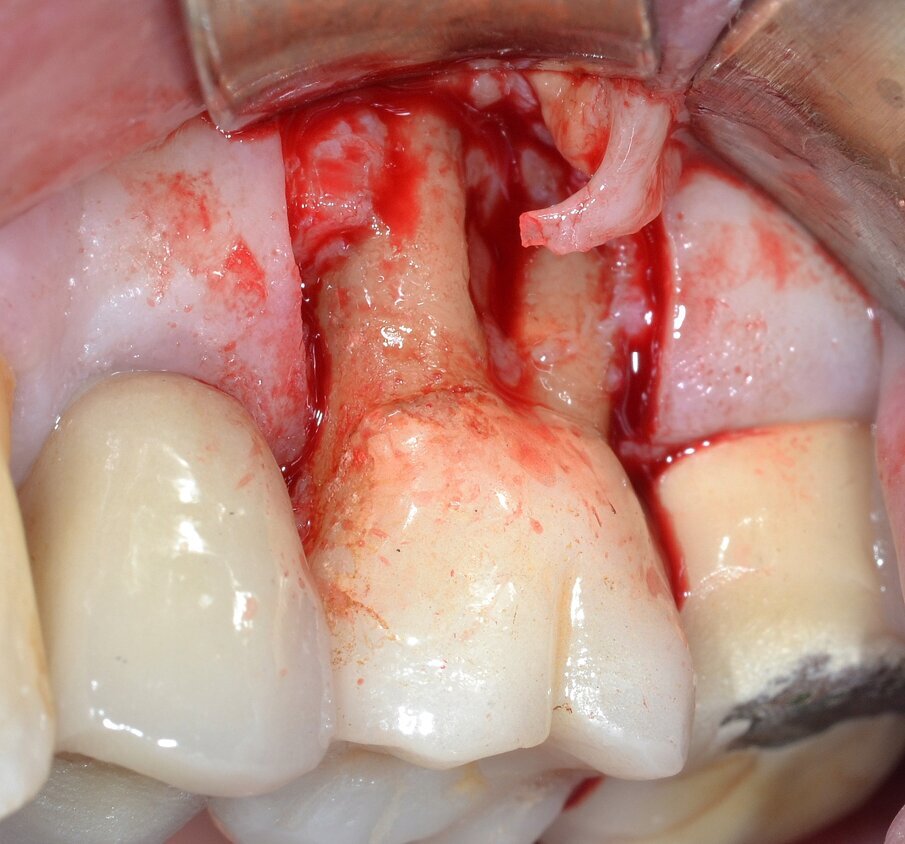

Il protocollo chirurgico di elezione consiste nell’eliminazione della forcazione stessa tramite procedura di rizectomia (ossia la sezione del complesso radicolare con l’eliminazione della/e radici giudicate non mantenibili) associata a resezione ossea e riposizionamento apicale del lembo: il complesso radicolare residuo sarà poi finalizzato mediante una protesi di tipo fisso. Dopo aver effettuato un’analgesia locale per infiltrazione con Articaina 1:100.000 con vasocostrittore si procede al sollevamento di un lembo a tutto spessore con lo scopo di accedere alla lesione parodontale: è possibile rilevare un importante difetto osseo che coinvolge la forcazione buccale (Fig. 4). La separazione delle due radici viene effettuato mediante frese diamantate o al carburo di tungsteno montate su manipolo ad alta velocità o su turbina: la sezione inizia nella zona del tetto della forcazione e si approfondisce verso l’interno facendo attenzione che l’angolo di inclinazione della fresa sia coincidente con l’asse lungo del dente (Fig. 5). L’eliminazione della radice mesio-buccale (Fig. 6) permette di ispezionare visivamente lo stato del complesso radicolare residuo, le cui condizioni depongono per una prognosi favorevole al mantenimento dell’elemento dentario nel tempo (Fig. 7).

Fig. 4 - Lembo di accesso a spessore totale: coinvolgimento della forcazione radicolare buccale di Classe 3 secondo Hamp & Nyman.